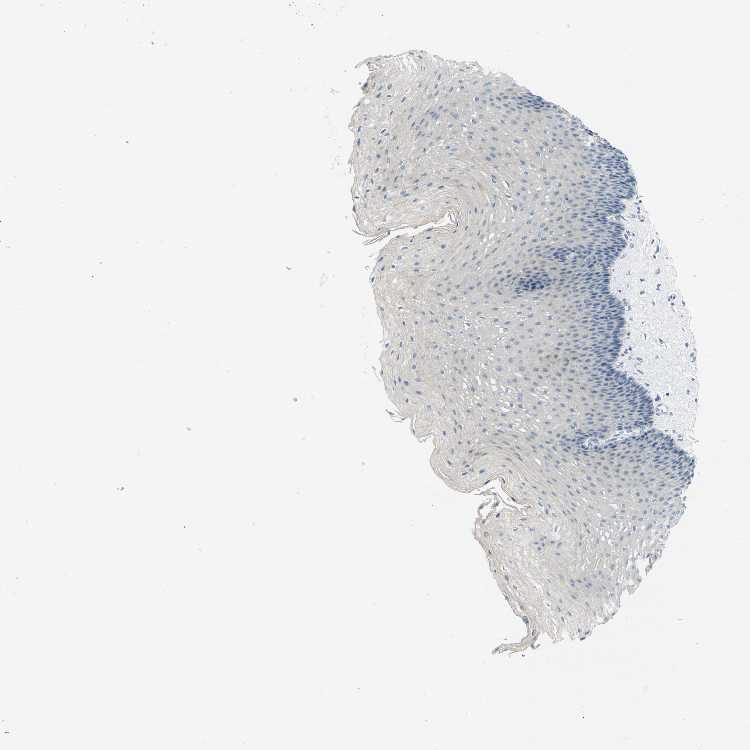

ESOPHAGUS - Antibody stainingi

Antibody staining in the annotated cell types in the current human tissue is reported as not detected, low, medium, or high, based on conventional immunohistochemistry profiling in selected tissues. This score is based on the combination of the staining intensity and fraction of stained cells.

Each image is clickable and will lead to virtual microscopy that enables deeper exploration of all samples and also displays staining intensity scores, fraction scores and subcellular localization as well as patient and tissue information for each sample.

Antibody HPA013547Antibody HPA013970Antibody HPA015066

Squamous epithelial cells Not detectedNot detectedNot detected